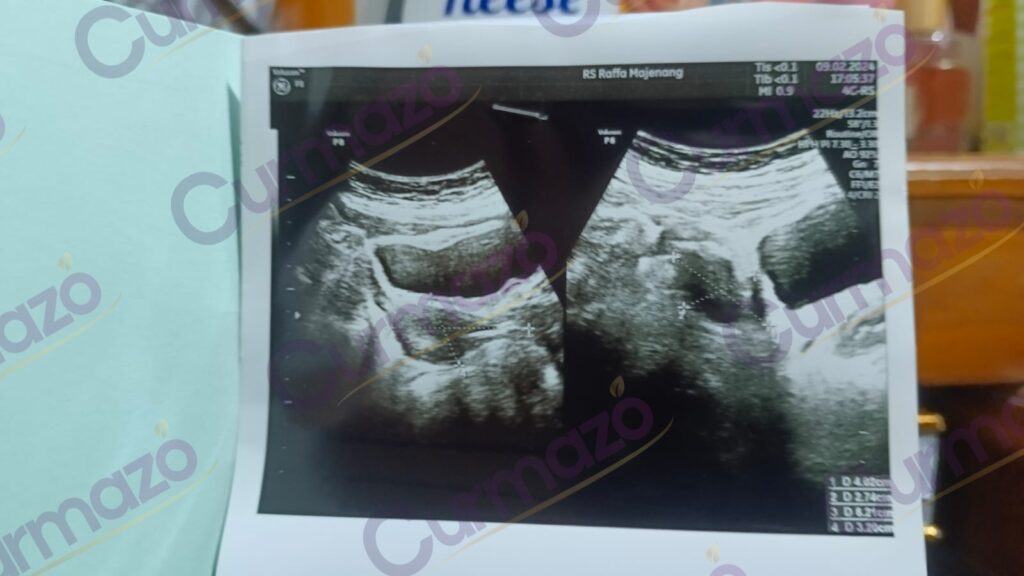

22 Februari 2024, saya mulai mengkonsumsi herbalnya sesuai dengan dosis yang diberikan dan juga dipandu untuk mengubah pola makan saya.

2 bulan konsumsi herbal, saya merasa kondisi saya semakin membaik sehingga saya melakukan pemeriksaan USG. Kata dokter kista saya sudah mengecil menjadi 3 cm.